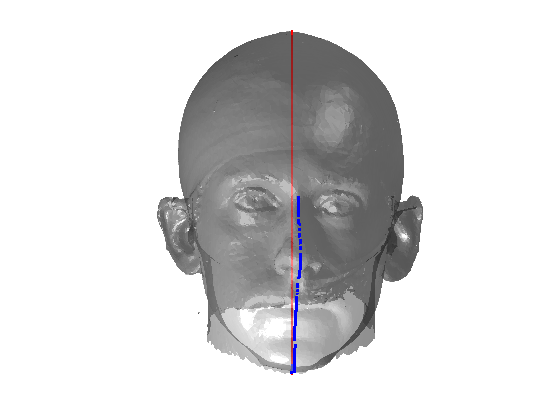

Fig. 9 shows examples of the fitted model (trained on FRGC data) on the first four subjects in our Headspace training set. Note that the mean of the landmarks in the sparse model is centred on the orgin, and so the scan data is moved towards that and becomes frontal in pose. We note that other researchers [28] have used 3D landmark localisation to find the head, but often this only includes landmarks that are relatively easy to localise, namely inner eye corners and nose. Localising more landmarks over a wider facial area has a number of advantage in terms of cropping, pose normalisation and global 3D template warping, all of which are described later.

|

|

|

|